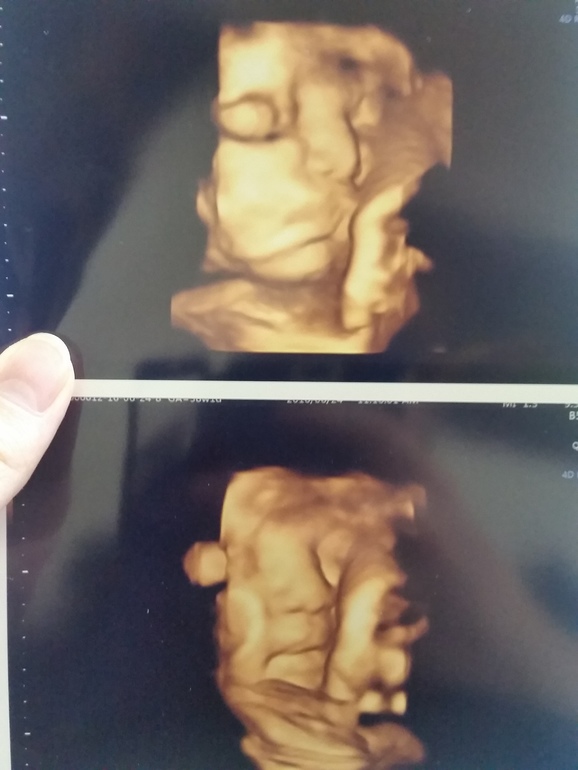

39я неделя

вот такие мы уже большие. 3кг! делал сосательные движения губками,такой хорошенький!